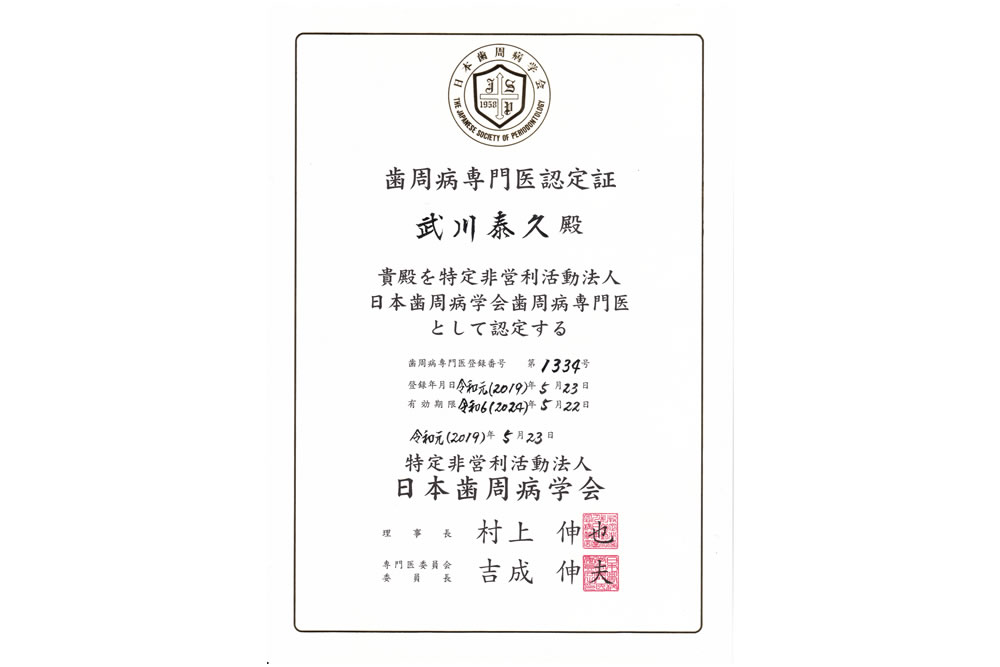

③ 日本歯周病学会「専門医」による精密・歯周病治療

抜歯の原因No.1である歯周病。この治療の成功率を高めることが抜歯回避の最重要要素となります。

抜歯の原因No.1である歯周病。この治療の成功率を高めることが抜歯回避の最重要要素となります。

BiVi歯科・矯正歯科では歯周病を専門に学ぶ学会であり、重度歯周病治療の名医の集団である「日本歯周病学会」の専門医認定を受けた歯周病治療のスペシャリストである歯周病専門医が担当いたします。

「抜かずに残す歯周病治療」に徹底的にこだわって15年、歯がグラグラしている、他医院様で抜歯を宣告された方、重度歯周病治療の名医をお探しの方はぜひ無料相談にお越しください。

歯周病専門医は、歯科医1000人中8人、全体の1%の歯周病治療名医

歯科医師は全国で14万人程度いるとされています。日本歯周病学会の専門医は、約1300名登録されていることから、歯科医師全体のわずか1%しかいない計算であり、歯周病治療の名医といえます。

歯科医師は全国で14万人程度いるとされています。日本歯周病学会の専門医は、約1300名登録されていることから、歯科医師全体のわずか1%しかいない計算であり、歯周病治療の名医といえます。

※埼玉県内の日本歯周病学会専門医は40名弱(2025年11月現在)

埼玉県内でわずか40名弱のみ。「日本歯周病学会専門医」とは?

日本歯周病学会の専門医資格は厚生労働省が認めている4つの専門医資格の一つで、非常に取得難易度が高いことで知られています。まず、日本歯周病学会の会員になり、その後、認定医→専門医と段階を経ての取得が義務付けられています。それでは歯周病専門医の資格取得難易度を見てみましょう。

日本歯周病学会の専門医資格を取得するには、日本歯周病学会指導医のもとで5年以上(私の場合は9年間)歯周病学に関する専門的な知識と臨床経験を積まなければなりません。

研修を始めて3年後に初めて「歯周病認定医」の受験資格が得られます。受験には中等度以上の歯周病を治療した資料を1つ提出することと、ペーパー試験があります。ペーパー試験は歯周病に関する基礎的な内容から学術的な内容まで幅広く出題されます。しかし、比較的初歩的な資格であるため「歯周病認定医」の合格率は90%と言われています。

歯周病認定医の資格取得後さらに2年以上指導医のもとで研修を行ったり、学会での発表や参加などの活動を行ったりすることで、やっと「歯周病専門医」の受験資格を得ることができます。

専門医の受験には重度の歯周病や特殊な歯周病を治療した証拠の資料10症例の提出が条件に入っております。10症例という数字は少なく感じるかもしれませんが、歯周病学会が設けている提出症例の基準が非常に厳しく、数百におよぶ症例をこなさなければ満たすことができません。この試験で約50%が不合格になります。

症例の診査を通過した後は、複数の歯周病指導医の前で症例に関するプレゼンテーションを行います。指導医による質疑は非常に鋭く、歯周病に関することはもちろんのこと、補綴(入れ歯やつめ物治療等)や歯内療法(根管治療)に至るまで幅広く深い知識を蓄えていかなければ的確に答えることができません。この試験を合格するのはわずか30%と言われています。この時点で合格できるのは受験者全体の10%台です。

「週刊朝日」に信頼できる歯周病専門医として取り上げられました